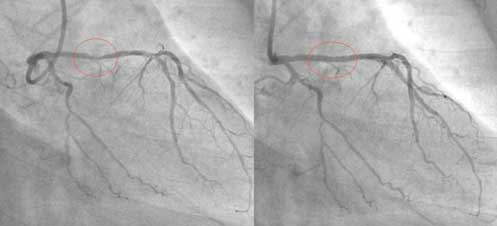

这位 Hakim让他自己在家中做一个食疗,他吃了一个月。一个月后他去同一家医院做检查,发现三条血管干干净净,原来堵塞的地方已经全通了。他是一位虔诚的回教徒,为了让更多的人受益,他把自己的经验放在网上分享,他的前后两张血管照片也放了在网上,在照片中,服用食疗之前与之后的分别连普通人也看得出来。